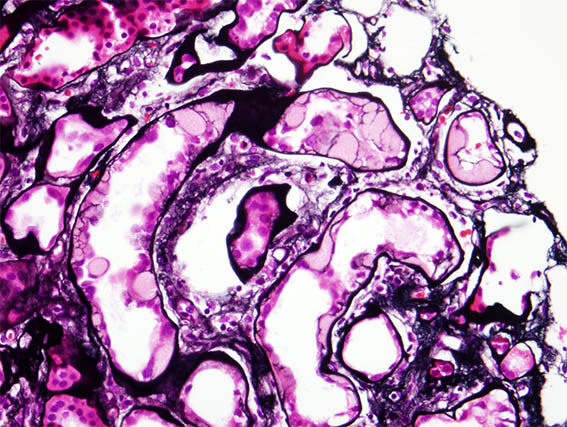

Una paciente de 41 años con diabetes mellitus de larga evolución desarrolló síndrome nefrótico abrupto, por lo que se le realizó una biopsia renal. La biopsia muestra nefropatía diabética avanzada sin GN superpuesta.

En una zona se identificaron lesiones tubulares como las que se ven en las siguientes imágenes:

Figura 4. Plata-metenamina, X400.

Inmunofluorescencia directa: positividad lineal para IgG en basales tubulares y glomerulares (característica de nefropatía diabética), sin otros depósitos. La tinción para kappa y lambda fue similar a la de IgG. Tinción de rojo Congo: negativa.